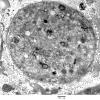

PERIPHERAL NEUROPATHY

4 AXONAL DEGENERATION

3 Electron Microscopy (2)